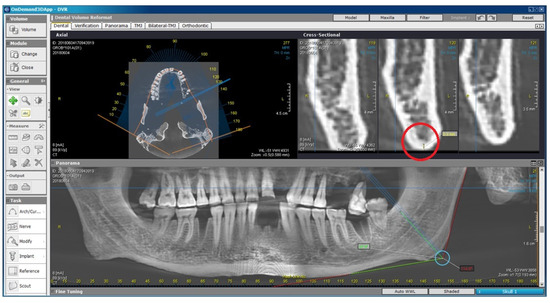

2.2. Radiomorphometric Assessments